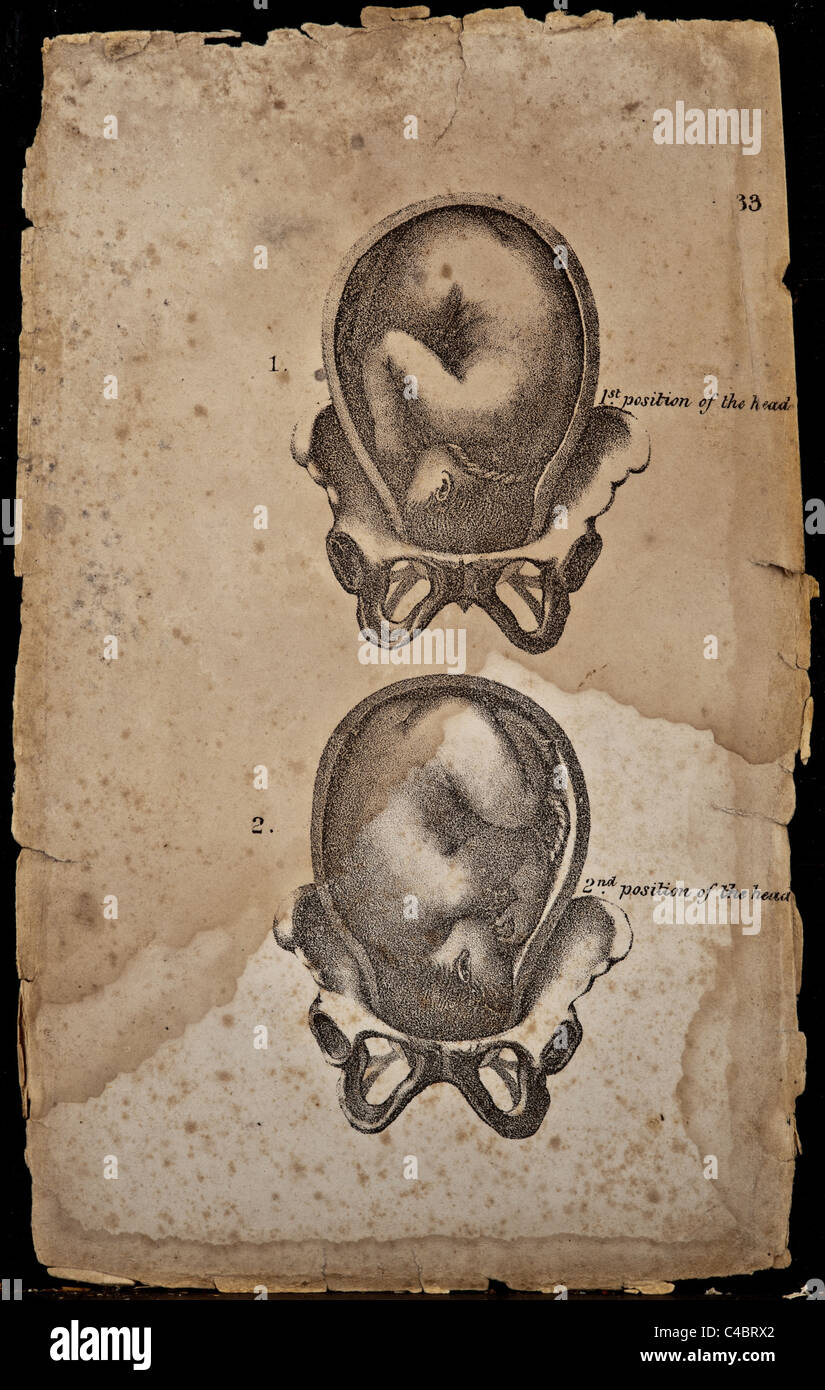

This is the two positions of an infant while in the uterus. copyright 1844 Stock Photohttps://www.alamy.com/image-license-details/?v=1https://www.alamy.com/stock-photo-this-is-the-two-positions-of-an-infant-while-in-the-uterus-copyright-37139594.html

This is the two positions of an infant while in the uterus. copyright 1844 Stock Photohttps://www.alamy.com/image-license-details/?v=1https://www.alamy.com/stock-photo-this-is-the-two-positions-of-an-infant-while-in-the-uterus-copyright-37139594.htmlRFC4BRX2–This is the two positions of an infant while in the uterus. copyright 1844